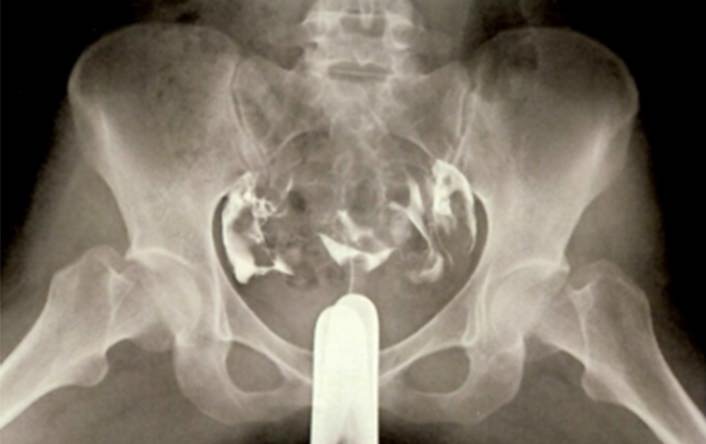

子宮卵管造影

子宮卵管造影検査(HSG)とは、子宮の入り口から造影剤を注入し、X線撮影をすることで、子宮の形と、卵子と精子が出会う通り道である卵管が詰まっていないか(通過性)を調べ、結果として一時的に妊娠しやすくなる効果も期待できる検査です。